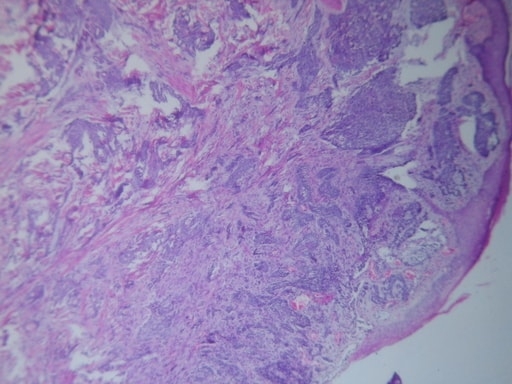

CARCINOMA MUCOCUTÁNEO